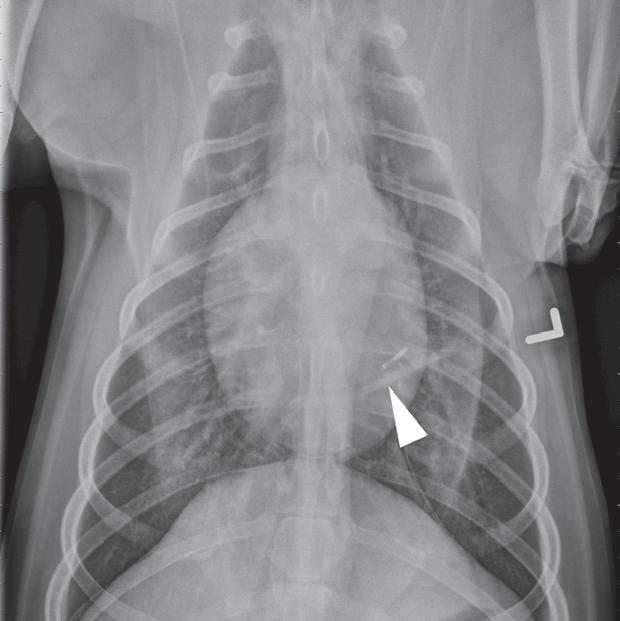

Rycina 4.6.4. Kardiogenny obrzęk płucny (kot) TK

Badanie wykonano u 4-letniej, kastrowanej samicy kota domowego krótkowłosego dializowanej z powodu niewydolności nerek. U pacjentki obserwowano echokardiograficzne objawy łagodnej kardiomiopatii. W momencie wykonywania tomografii komputerowej kot był umiarkowanie przeciążony płynami. Obraz na ryc. a jest reprezentatywnym obrazem na poziomie tylnej części klatki piersiowej, a obrazy przedstawione na ryc. b i c stanowią powiększenie ryc. a. Niewielka objętość płynu opłucnowego unosi powietrzne płuco (a – czarna strzałka). Widoczny jest łagodny, rozproszony wzrost atenuacji płuc z dodatkowymi, licznymi zmianami w typie matowej szyby. Wydaje się, że te ostatnie nacieki są najbardziej widoczne wokół naczyń płucnych (a–c – białe strzałki). Badanie pośmiertne potwierdziło, że nacieki były spowodowane obrzękiem płuc. W tym przypadku obrzęk prawdopodobnie był wynikiem względnej niewydolności komór serca spowodowanej kardiomiopatią i przeciążeniem płynami